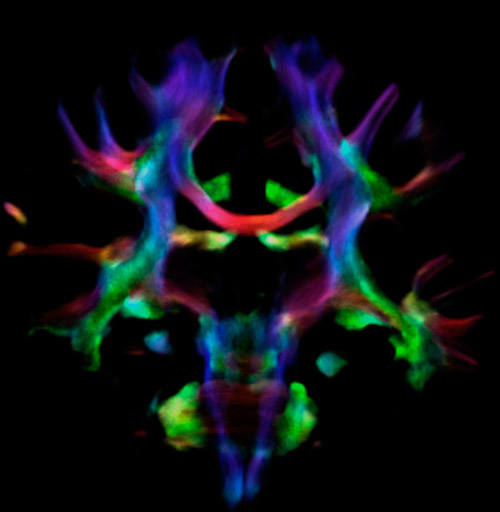

All images were created from the same acquisition in a child using Ingenia 3.0T CX and 32-channel dS Head coil. Diffusion data was acquired at b-values 0, 500, 1000, 2000, 3000. The use of high b-values (3000 s/mm2) effectively suppresses extra-axonal water signal and provides high angular resolution.

Fiber orientation density

CSD of multishell DWI results in the white matter FOD at each voxel. Unlike the conventional diffusion tensor model, this approach enables accurate modeling of multiple fiber populations within a single voxel.

Crossings of the corpus callosum, corticospinal tracts, and the superior longitudinal fasciculus are shown.

Crossing fibers of the corpus callosum bordered by the superior longitudinal fasciculus as well as within in the pons.